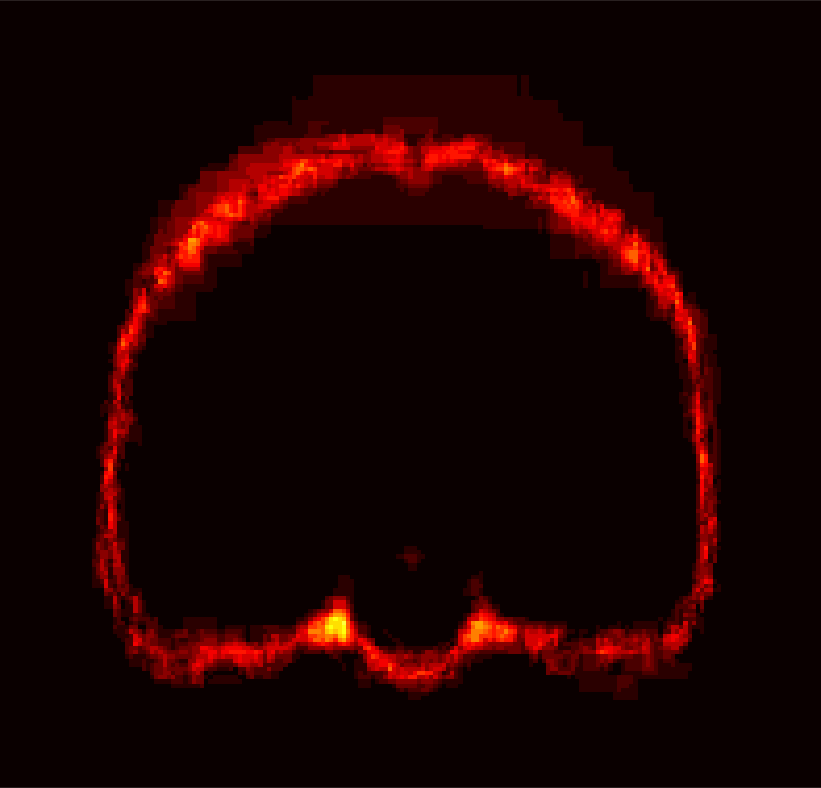

[Uncaptioned image] [Uncaptioned image] [Uncaptioned image] [Uncaptioned image]

(a) (b) (c) (d)

Figure 8: Example BRATS image with its decomposition result in atlas space. (a) Input image after pre-processing; (b) quasi-normal image L+M𝐿𝑀L+M; (c) non-brain image S𝑆S; (d) pathology image T𝑇T.

In addition to extracting the brain from pathological datasets, our method also allows for the estimation of a corresponding quasi-normal image in atlas space, although this is not the main goal of this paper. Fig.8 shows an example of the reconstructed quasi-normal image (L𝐿L) for an image of the BRATS dataset, as well as an estimation of the pathology (pathology image T𝑇T and non-brain image S𝑆S). Compared to the original image, the pathology shown in the quasi-normal image has been greatly reduced. Hence this image can be used for the registration with a normal image or a normal atlas. This has been shown to improve registration accuracy for the registration of pathological images [27]. Furthermore, an estimate of the pathology (here a tumor) is also obtained which may be useful for further analysis. Note that in this example image the total variation term captures more than just the tumor. This may be due to inconsistencies in the image appearance between the normal images (obtained from OASIS data) and the test dataset. As our goal is atlas alignment rather than quasi-normal image reconstruction or pathology segmentation, such a decomposition is acceptable, although we could improve this by tuning the parameters or applying regularization steps as in [27].